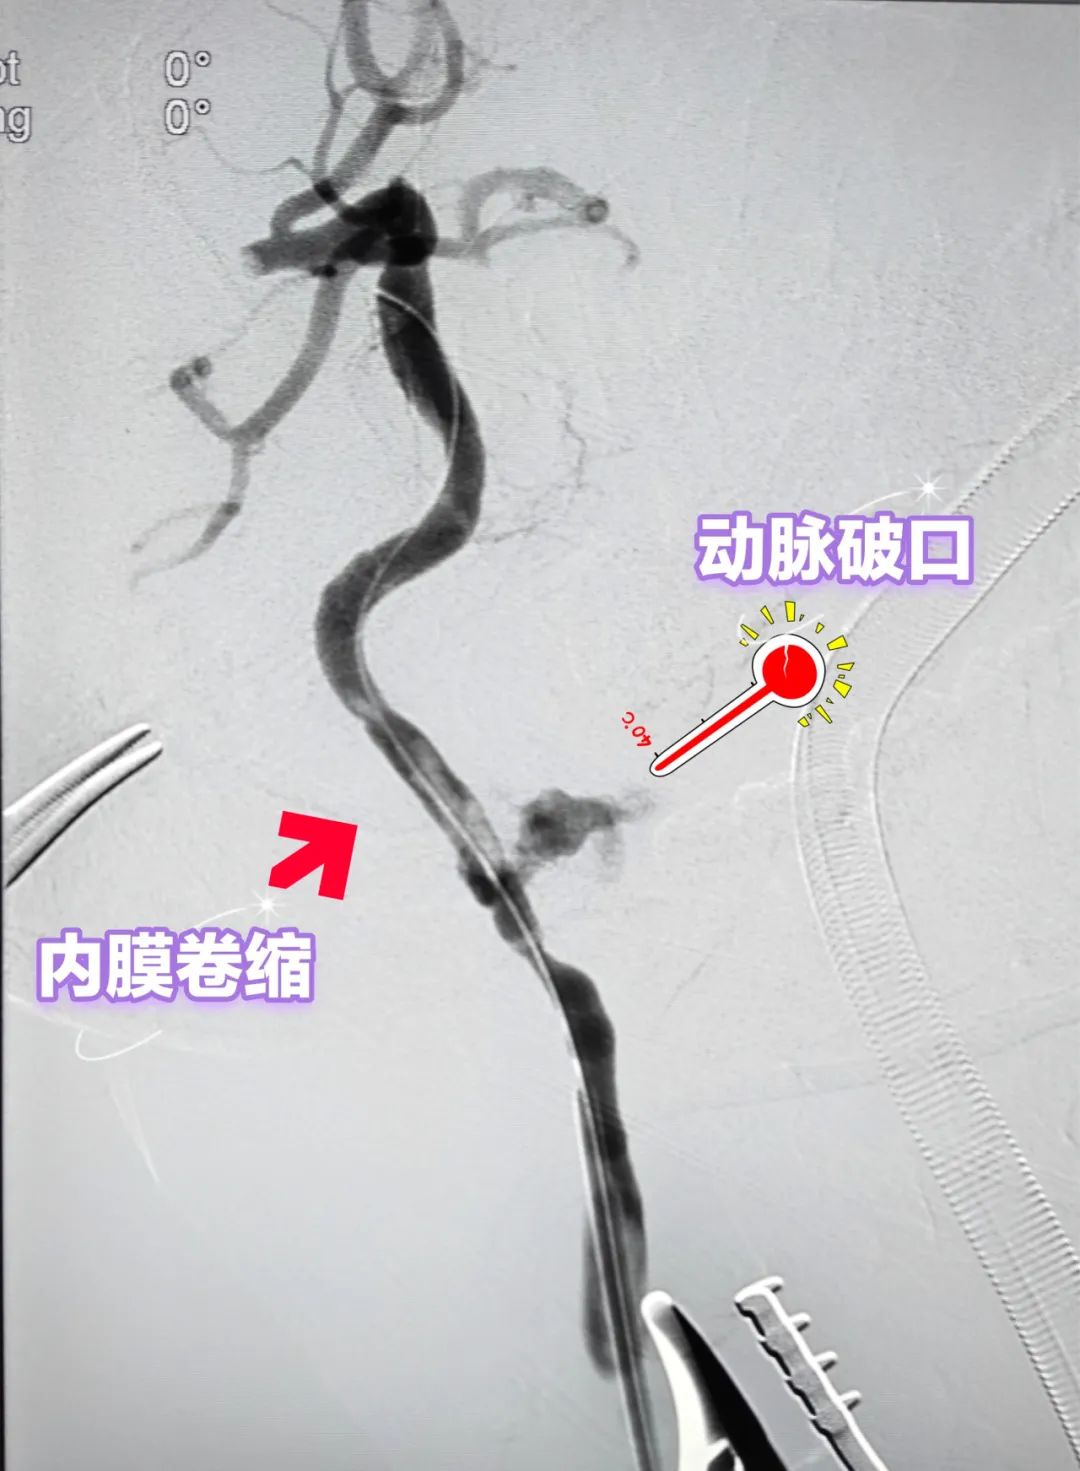

经过2个多小时奋战,张铠医生带领医疗团队切开右颈动脉并快速、准确地定位颈内动脉破裂口,数字减影血管造影下谨慎地取出残端血栓后,熟练地运用导丝导管扭控技术通过内膜卷缩处及动脉破口,成功开通右颈内动脉,并利用复合手术技术使用覆膜支架精准封堵动脉破口,恢复了脑部血流同时顺利止血。